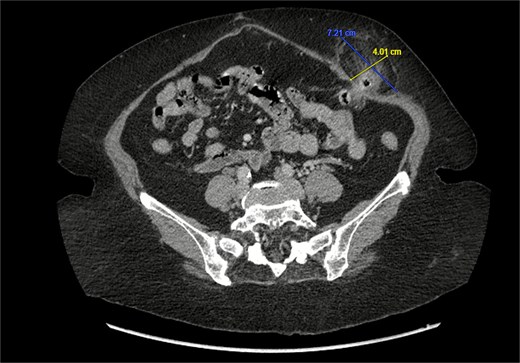

A 76-year-old female with a medical history of type 2 diabetes mellitus (controlled with oral medications), hypertension (on two medications), hyperlipidemia (on atorvastatin), and recently diagnosed Alzheimer’s disease (started on memantine) presented to the emergency department with severe left-sided abdominal pain of 2 days’ duration. The pain began gradually but worsened significantly in the last few hours. It was associated with a bulging mass in the abdomen that was tender and painful to touch. The patient reported that the swelling had been present for 2 years, intermittently reducible with minimal exertion. However, since the previous day, it had become irreducible and increasingly painful, particularly after a failed attempt to reduce it manually at home. She also admitted to chronic constipation for years, usually treated with oral laxatives, though she had not been compliant with them recently. Her surgical history included a laparoscopic cholecystectomy combined with paraumbilical hernia repair using mesh 3 years ago. Upon examination by the on-call surgical team, the patient was afebrile with stable vital signs. Her abdomen was distended, and a 7 × 7 cm irreducible, tender mass was noted over the left side. An urgent computed tomography (CT) scan of the abdomen and pelvis with intravenous and oral contrast revealed a left lateral ventral abdominal hernia traversing the left lateral oblique muscles. The hernia sac contained omental fat and an inflamed diverticulum of the transverse colon, with surrounding inflammatory changes. The defect measured 1.4 × 1 cm, and the hernia sac measured 6.7 × 4.2 × 4 cm. No free fluid, fluid collections, or pneumoperitoneum were identified (Figs 1–3).

Sagittal section of CT abdomen and pelvis showing the ventral hernia.